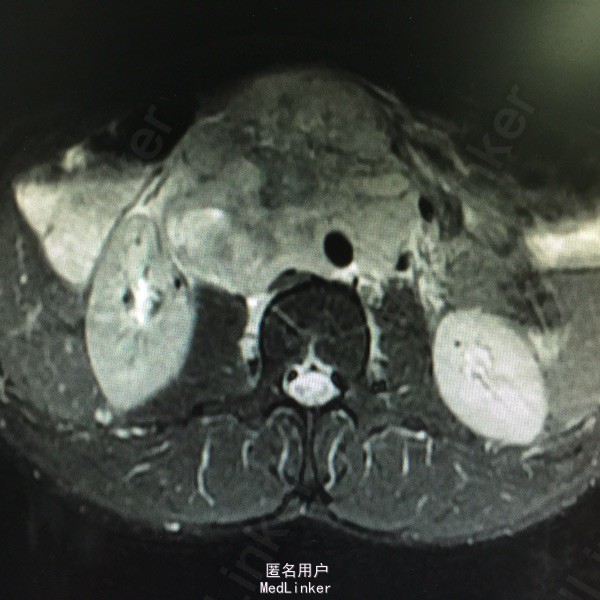

查体:上腹少许压痛,中腹部可门机一大小约8*8cm的肿物,质地硬,活动性差,无明显按压痛。其余无特殊。 辅助检查:腹部MR:1.腹膜后占位(80*92*147cm),考虑淋巴瘤可能性大,病灶推压下腔静脉、门静脉主干及胰腺,包绕腹主动脉、肠系膜上动脉、双侧髂血管及双侧肾动脉,双侧肾静脉显示不清。2.肝左叶内胆管轻度扩张。胃镜示:1.慢性浅表性胃窦炎,2.胃窦粘膜隆起待查:异位胰腺?B超引导下行肿物穿刺活检术,病理结果示:符合生殖细胞来源恶性肿瘤,考虑精原细胞瘤可能性大。后完善盆腔CT示:1.右侧睾丸肿物,性质为恶性肿瘤,考虑为精原细胞瘤可能,阴囊右侧积液,腹膜后、肠系膜根部、盆腔内多发淋巴结转移,不除外累及胰头、体部、右侧腰大肌可能,下腔静脉、双侧髂总、内静脉、右髂外静脉、股静脉腔广泛栓子形成;盆腔少量积液。

诊断考虑精原细胞瘤。予全麻下右侧睾丸切除术,术后予BEP方案化疗,并予抗血小板治疗。

患者3程化疗后复查CT评估PR:腹膜后大血管周围、盆腔内可见多发肿大淋巴结影,部分融合成团,最大层面范围为52*29cm,较前明显缩小。 精原细胞瘤起源于睾丸原始生殖细胞,为睾丸最常见的肿瘤,多发生于中年以后,常为单侧性,右侧略多于左侧。发生于隐睾的机率较正常位睾丸高几十倍。该瘤为低度恶性。高剂量强度的BEP方案(博来霉素+依托泊苷+顺铂)仍是低危生殖细胞肿瘤的最佳治疗方案。